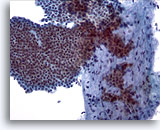

Figure 29

Breast FNA, Ductal carcinoma in situ.

Clusters of fairly bland tumor cells are noted. A vague impression of a fibrovascular core is noted in the cell group on the right. 40x

Figure 29

Breast FNA, Ductal carcinoma in situ.

Clusters of fairly bland tumor cells are noted. A vague impression of a fibrovascular core is noted in the cell group on the right.

40x